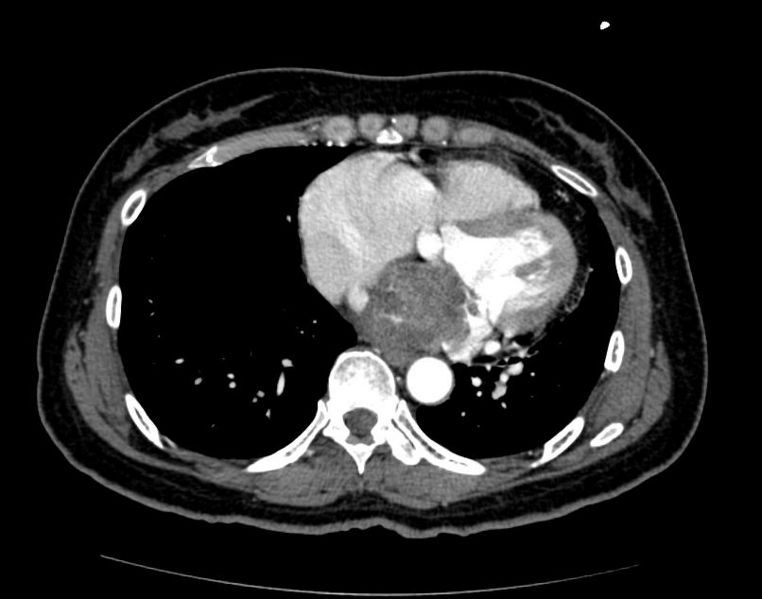

Cardiac Tumors CT - Wikidoc

www.wikidoc.org

www.wikidoc.org

cardiac rhabdomyosarcoma ct tumors wikidoc

Rhabdomyosarcoma computed tomography magnetic imaging observations resonance neck head figure ol. Rhabdomyosarcoma alveolar metastatic axial obtained. Cardiac tumors ct